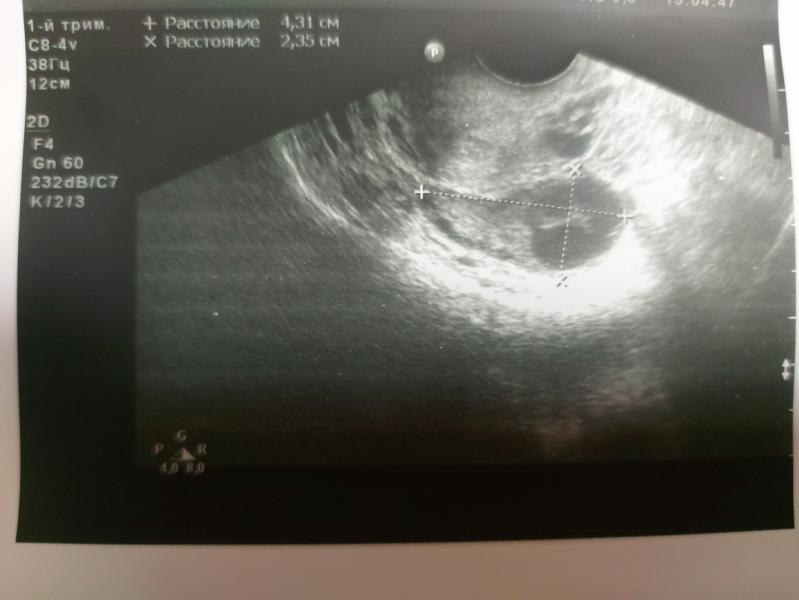

Добрый вечер, девчонки! Сходила сегодня к врачу, т.к. заметила насколько коричневых капелек. Сделали узи, ни отслоек, ничего подобного нет. Возможно из-за недавней прогулки на 5,5 км, похоже какой-то сосудик разорвался. Единственное, что меня смущает, врач для подстраховки, без сдачи анализа на гормоны назначил Дюфастон 3 таб/день.

Размер ПЯ - 4,5 мм

Размер эмбриона - 1,5...1,8 мм

Размер ЖМ - 1,2 мм